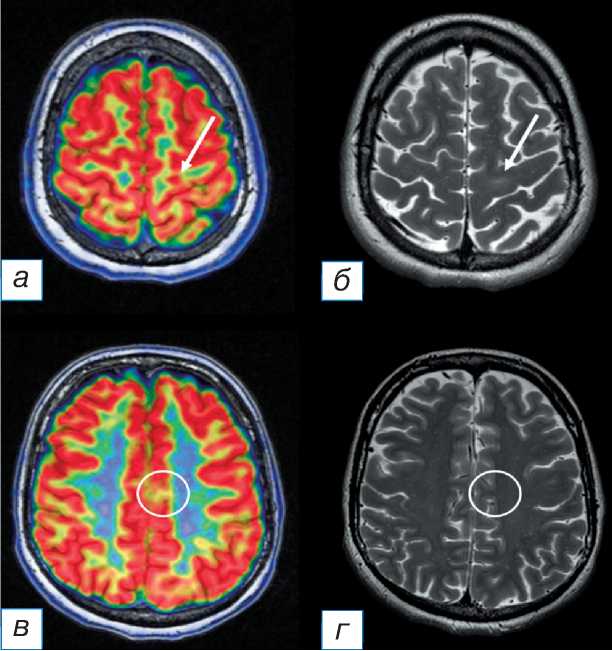

У 2 пациентов с ФКД теменной локализации зона гипометаболизма 18F-ФДГ не совпадала с локализацией структурных изменений на МРТ, но располагалась в соседних участках вещества мозга (рис. 2, 3). При проведении этим пациентам стерео-ЭЭГ-ВМ эпилептиформная активность определялась в зоне выявленных структурных изменений и не регистрировалась в зоне метаболических изменений.

формная активность, в 1 случае стерео-ЭЭГ-ВМ не выполнялась, после резекции ФКД был достигнут исход класса Engel II.

Рис. 3. Данные стереоэлектроэнцефалографии: за время мониторинга в течение 24 часов зарегистрировано 13 фокальных немоторных приступов с переходом в моторные с инициацией слева под электродом ‘PSF-PC’ (задняя верхняя лобная извилина — задняя часть поясной извилины, 8 контактов).